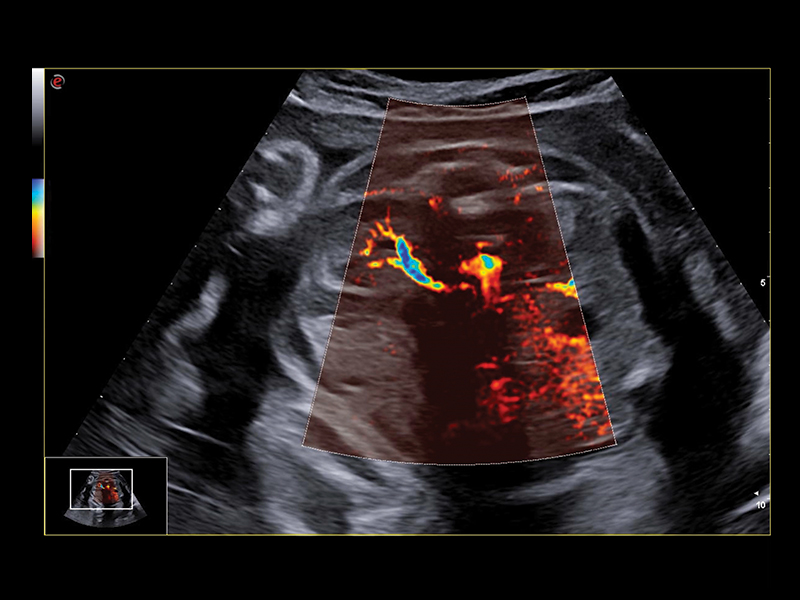

Advanced Vascularization Imaging in Obstetrics Ultrasound

Bright Flow is the new convenient color map for blood flow through a blood vessel.If traditional flow images display flows in thin and flat sections, Bright Flow, with its 3D-like appearance, lead to an easier and faster hemodynamic visualization, including the tiniest internal structures of the heart. Achieve a new level of precision with microV HighFR (High Frame Rate) and XFlow, Esaote’s latest alternatives to Color Doppler, and don’t miss the option of exploring fetal brain microvascularization.

Clinical Images